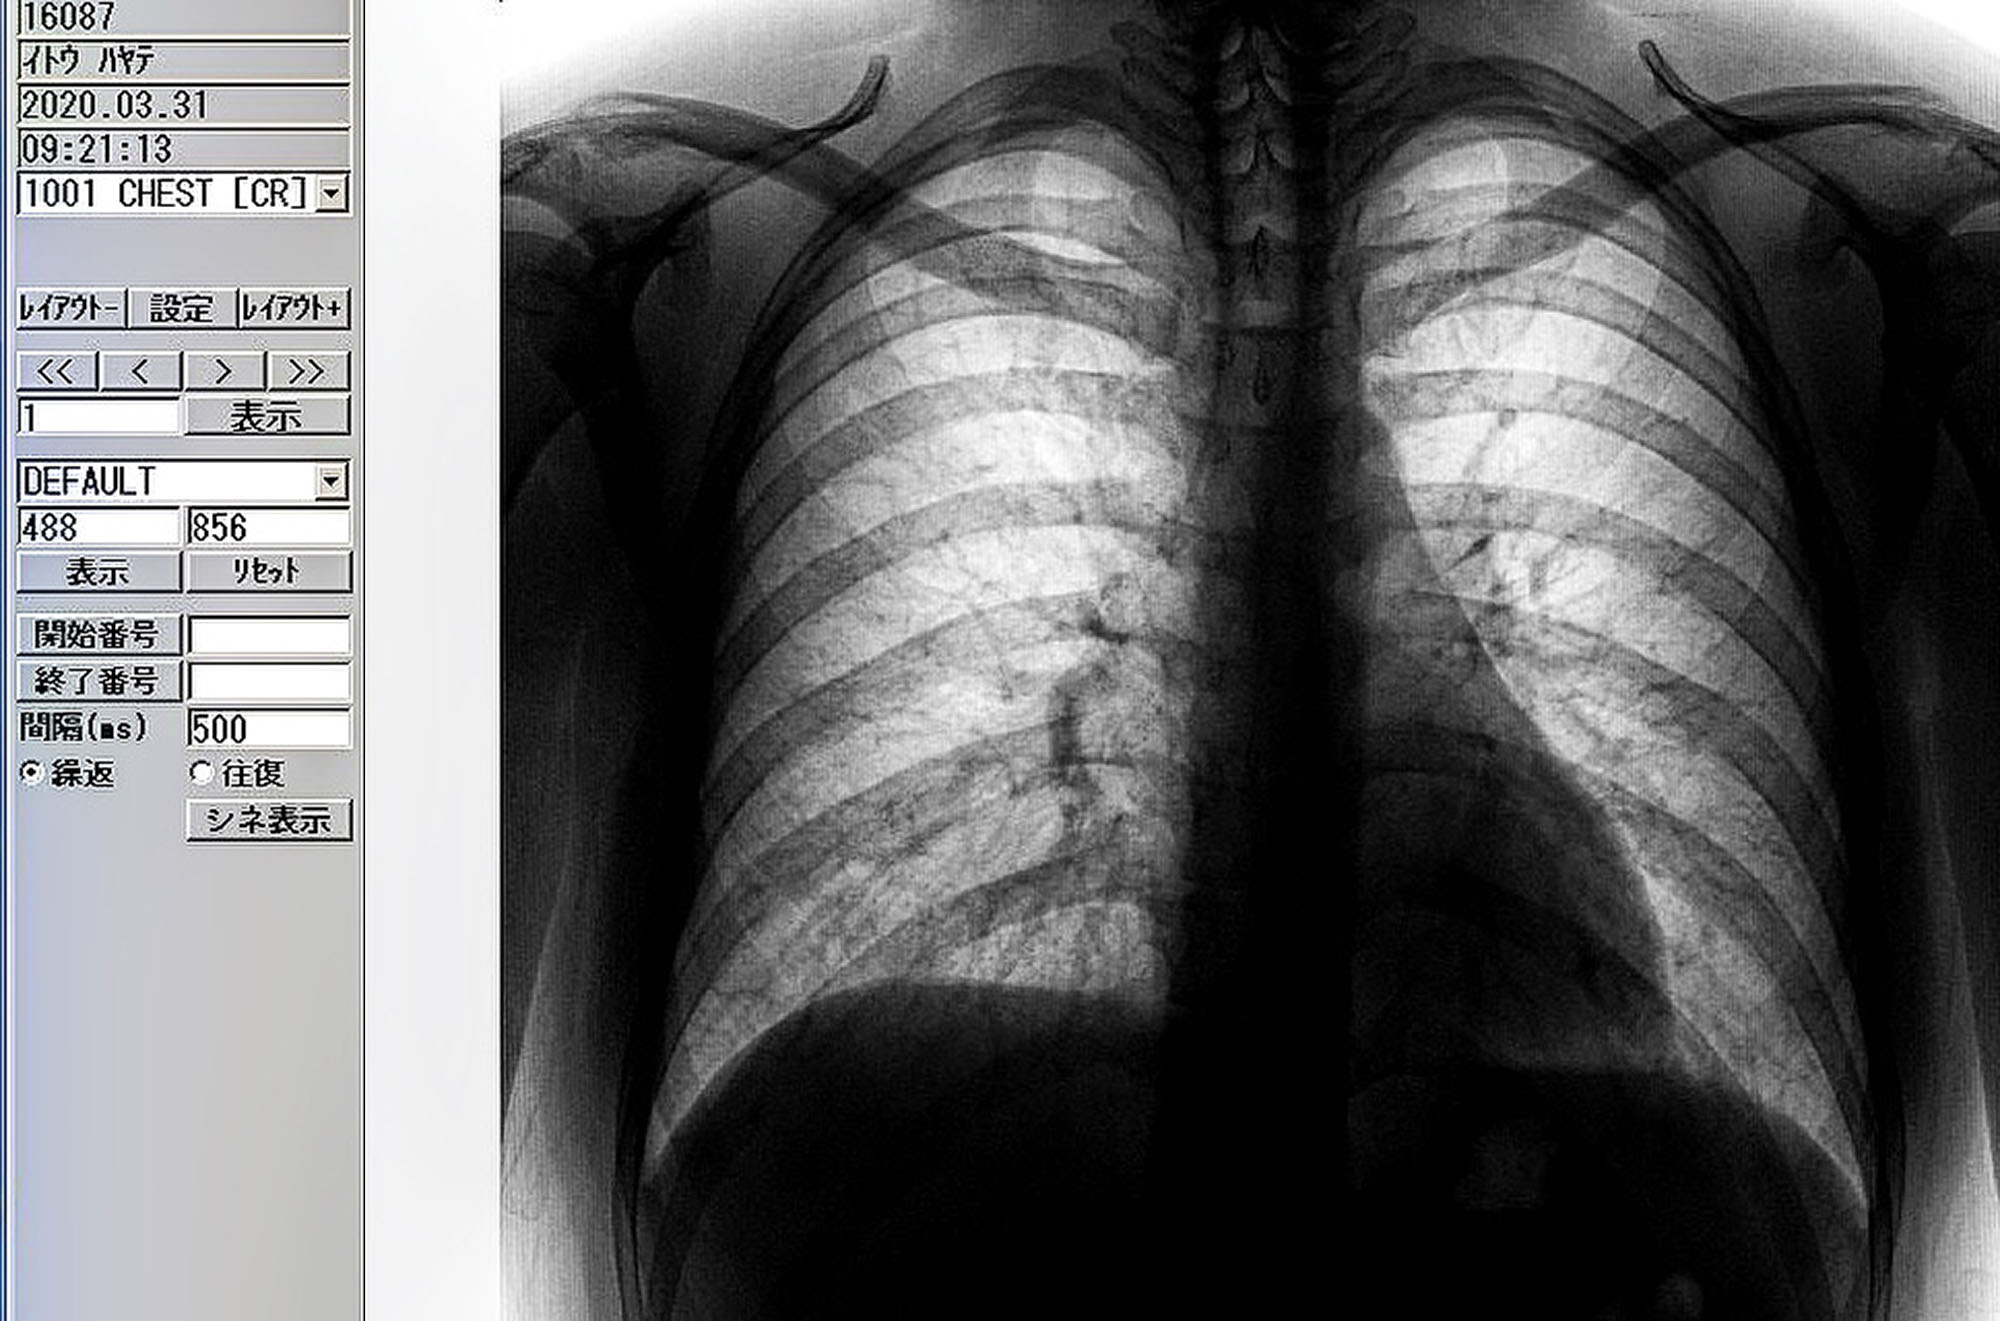

私が使用する写真はいわゆるただのリサーチをした結果の記録ではなく、記録であり暗号でありフィルムという物質である証明だ。そして私が世界に立ち向かう生の記録であるということが前提である。

写真はフィルムという物質だし、アートだと私は思っている。

写真とは視点を変えるだけで記録にもなり、抽象的や叙情的にもなり、物質にもなる。ただの複製可能なデータではない。